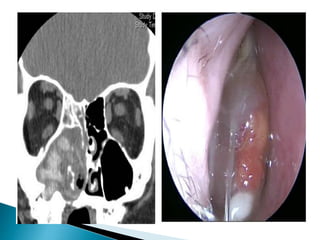

 Severe nasalcavity soft tissue thickening  Hypoattenuating mucosal thickening within lumen of paranasal sinus  Rapid aggressive bone destruction of sinus walls  Fungi can also spread along vessels with spread beyond the sinus with intact bony walls  Intracranial extension  cavernous sinus thrombosis  carotid artery invasion or occlusion

 Unilateral ethmoidinvolvement with bone destruction, intraorbital spread and proptosis

 Mass withinthe lumen of paranasal sinus  Frontal sinus most common followed by sphenoid sinus  Noncontrast CT – hyperattenuating mass often with punctate calcifications

 High densitymaterial with thickened walls of the maxillary sinus due to chronic inflammation